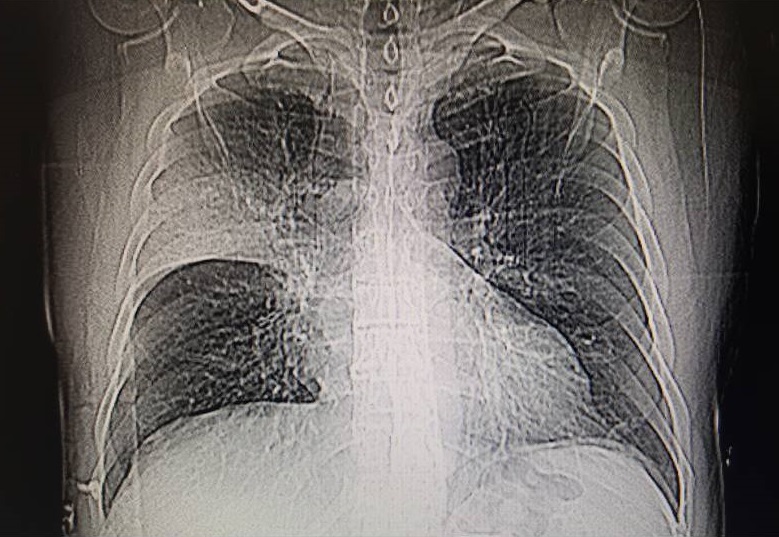

50 yaşında erkek hasta yurtdışındaki bir ülkeden geldiğini, 2-3 gündür öksürük ve kanlı balgam yakınması olduğunu ifade etti. Periferik kan incelemesinde lökosit 6800/mm3 (nötrofil 4700, lenfosit 1000), albümin 3.07, LDH 375 (RD: 135-225 Ü/lt), CRP 46 (RD: 0-5 mg/dl), ALT 95 (RD: 5-41), AST 121 Ü/lt, GGT 118 (RD: 8-61 Ü/lt) idi. Diğer biyokimyasal analizler normal sınırlardaydı. Akciğer grafisinde sağ üst lobdaki opasitenin minör fissür sınırına kadar ulaştığı ancak

fissürü geçemediği gözlenmekteydi (Resim 6). Fissürü geçemeyen tek lob konsolidasyon alanları bakteriyel pnömoniyi düşündürdü. Bu nedenle hastaya hidroksiklorokin, azitromisin ve seftriakson tedavisi başlandı. Ancak nazofaringeal sürüntü örneği COVID-19 pozitif olarak bildirildi. Bu olgu COVID-19’a bağlı alveoler eksüdanın fissürleri geçemeyebileceğini, COVID-19 pnömonisinde alveoler boşluktaki eksüdanın infektif natürden çok inflamatuar bir karakterde olabileceğini göstermektedir.